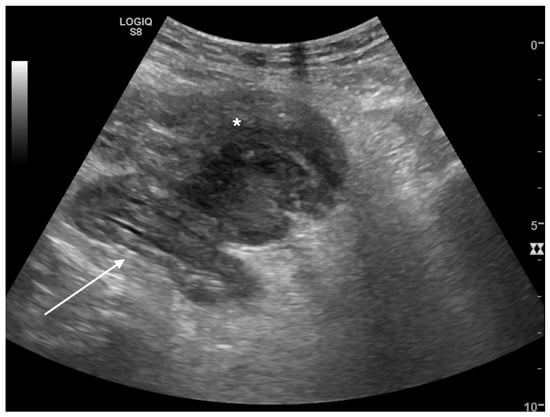

Intraparenchymal Fluid Lesions

| Intraparenchymal | Infected cyst Infectious cyst Hematoma Abscess Aneurysm Pseudoaneurysm |